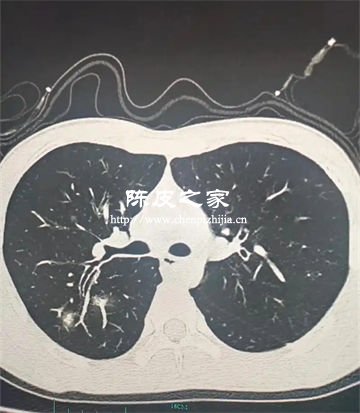

陳皮多糖對PM2.5致肺損傷的防護(hù)機(jī)制主要體現(xiàn)在抗炎作用、抗氧化應(yīng)激、抑制氣道重塑與纖維化、調(diào)節(jié)免疫微環(huán)境、減少顆粒物沉積與清除等方面。下面進(jìn)行詳細(xì)講解。

PM2.5顆粒物進(jìn)入肺部后,會(huì)刺激肺泡巨噬細(xì)胞和肺上皮細(xì)胞釋放炎癥因子(如IL-17A、TNF-α、IL-8),引發(fā)慢性炎癥和肺纖維化。陳皮多糖中的活性成分能顯著減少支氣管肺泡灌洗液中的炎癥細(xì)胞數(shù)量,降低炎癥介質(zhì)濃度,抑制MAPK/NF-κB信號通路中p38、JNK和p65的磷酸化,從而阻斷炎癥級聯(lián)反應(yīng),減輕肺部炎癥損傷。

PM2.5誘導(dǎo)的氧化應(yīng)激是肺損傷的核心機(jī)制之一,其產(chǎn)生的活性氧(ROS)會(huì)破壞細(xì)胞結(jié)構(gòu)和遺傳物質(zhì)。陳皮多糖通過直接清除自由基、增強(qiáng)抗氧化酶活性、調(diào)控氧化應(yīng)激相關(guān)蛋白等發(fā)揮抗氧化作用。

3.抑制氣道重塑與纖維化

PM2.5長期暴露會(huì)導(dǎo)致氣道杯狀細(xì)胞增生、黏液高分泌及纖維化,進(jìn)而引發(fā)肺氣腫和小氣道重塑。陳皮多糖可減少氣道黏液分泌,抑制膠原沉積和纖維化進(jìn)程,緩解PM2.5誘導(dǎo)的氣道結(jié)構(gòu)改變。